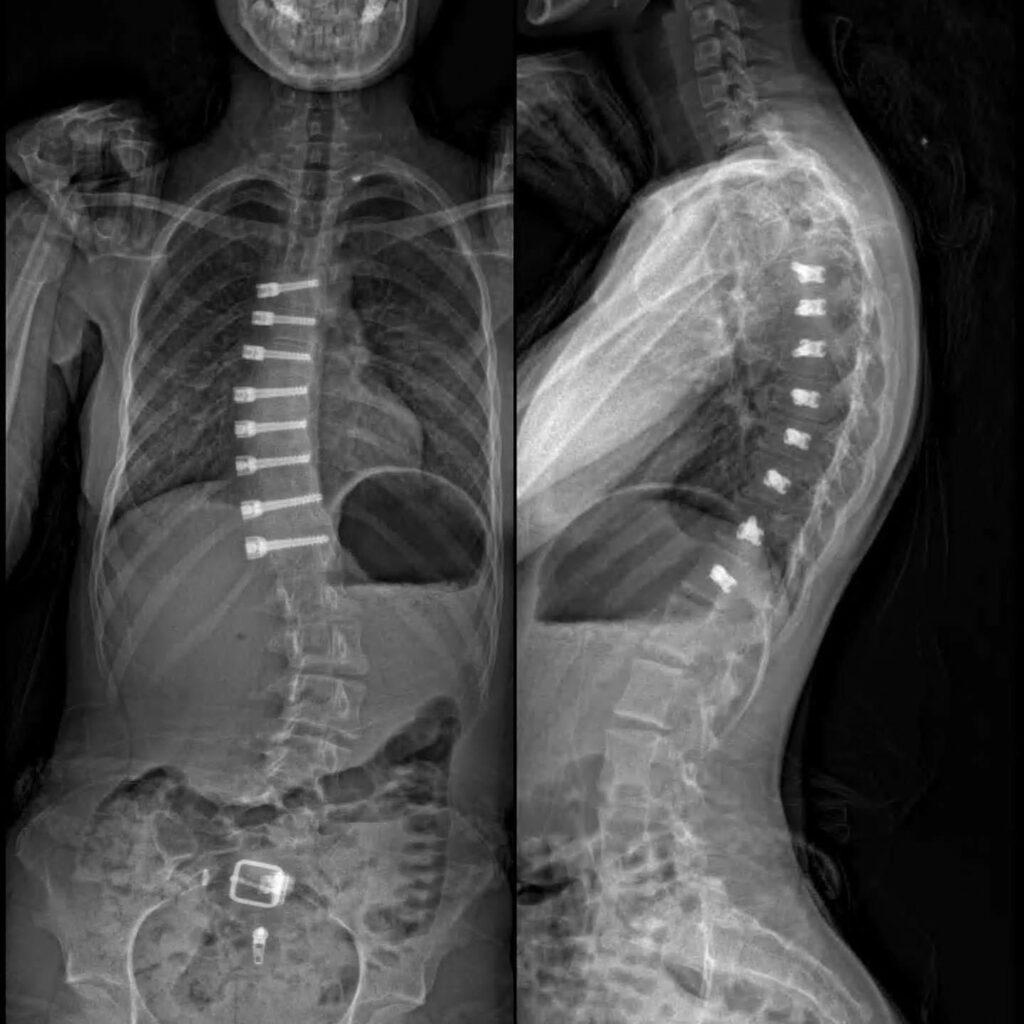

Pediatric scoliosis, far from being a mere cosmetic concern, represents a significant and often insidious challenge in pediatric orthopedics and primary care. Affecting a substantial percentage of school-aged children and adolescents, its early presentation can be subtle, yet its potential for rapid progression during critical growth spurts demands vigilant attention from healthcare professionals. Untreated or inadequately managed scoliosis can precipitate a cascade of serious physical sequelae, including chronic pain, respiratory compromise, and, in severe cases, neurological deficits. Furthermore, the psychosocial burden on young patients, encompassing body image dissatisfaction and reduced quality of life, adds another critical dimension to its overall impact, underscoring the profound importance of timely diagnosis, precise evaluation, and a multidisciplinary approach to management for optimizing long-term health and well-being. Visit - Pediatric Scoliosis Fort Lauderdale